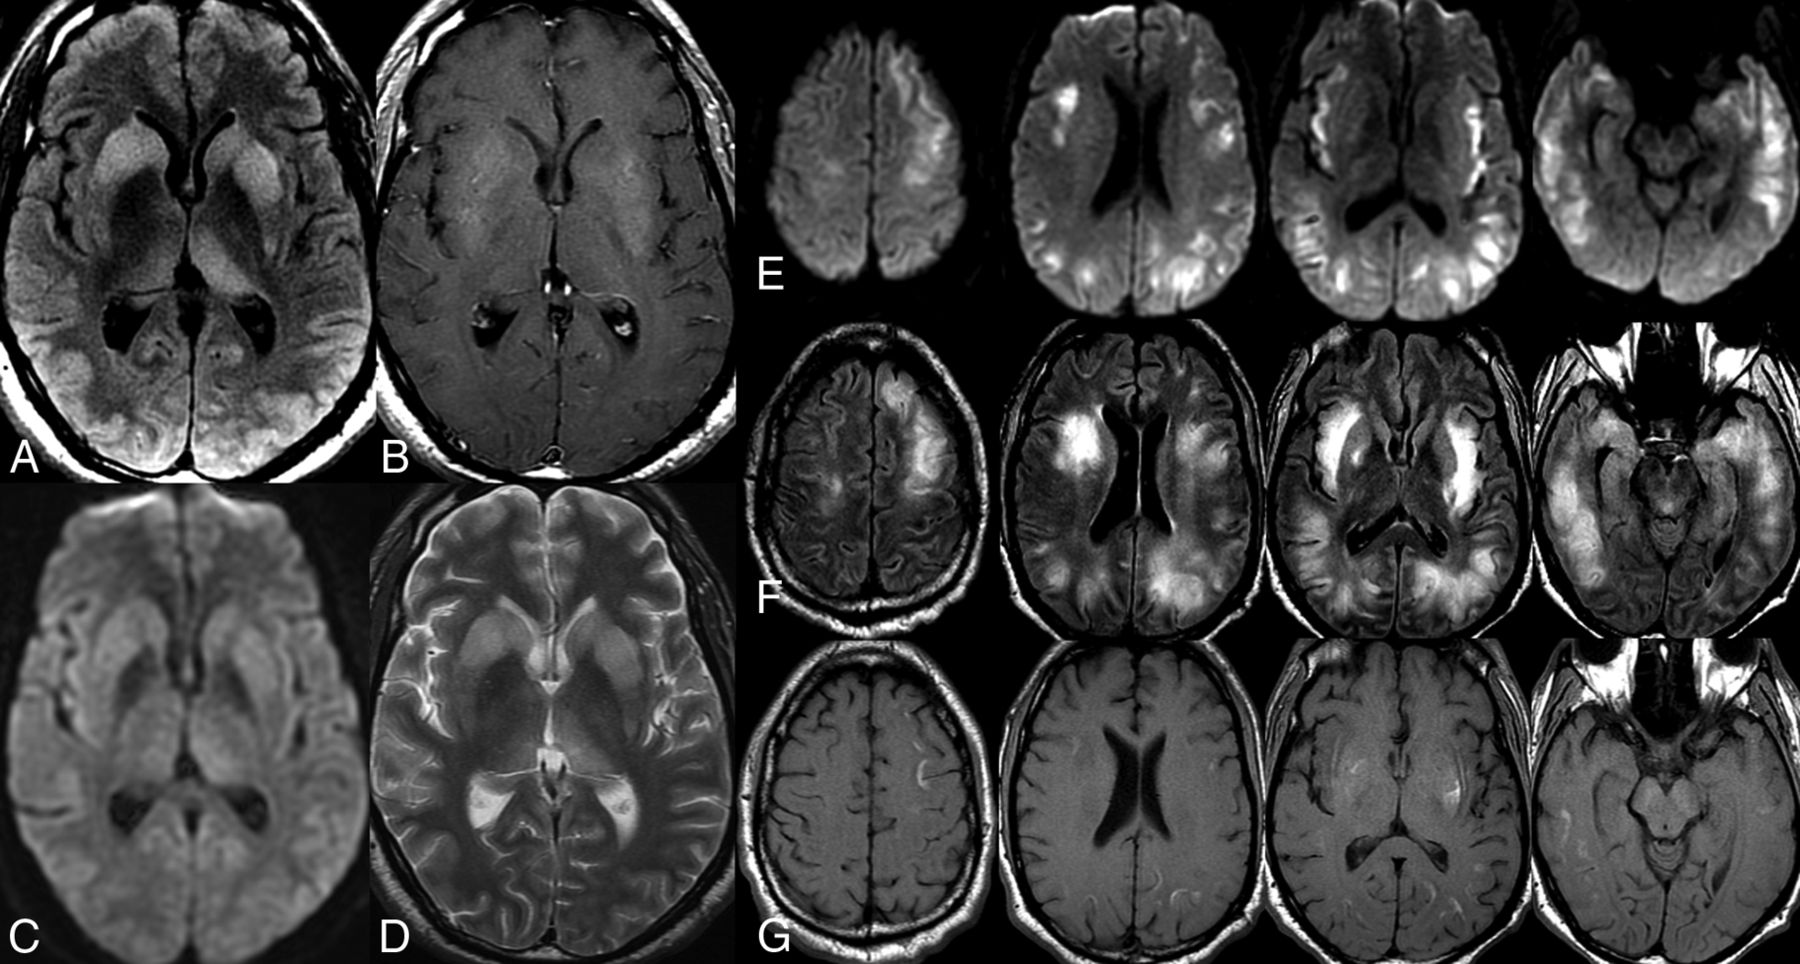

A 38-year-old man presented with progressively worsening cognitive impairment, orofacial dyskinesia, and bilateral upper extremity chorea. MR imaging of the brain demonstrated bilateral symmetric T2/FLAIR hyperintensity of the dorsal striatum (caudate and lentiform nucleus) without restricted diffusion or postcontrast enhancement (Fig 6A–C and E). The autoimmune work-up was extensive but was initially negative for serum autoantibodies, including anti-dsDNA antibodies. He underwent a 3-day pulse IV steroid regimen with prednisone taper that resulted in gradual symptom improvement during 2–3 weeks but with persistent striatal T2/FLAIR abnormalities on the follow-up MR imaging of the brain, which also demonstrated interval development of some intrinsic T1 hyperintensity in the left striatum (Fig 6D). He was initially transferred to subacute rehabilitation but was readmitted for plasmapheresis when serum antibody testing was positive for anti-NMDAr antibodies. He completed 5 rounds of plasmapheresis with a good response. Follow-up MR imaging of the brain demonstrated reduced T2/FLAIR signal abnormality with atrophy of the caudate heads and persistent left striatal T1 hyperintensity (Fig 6H). Note that this patient did not have SLE or anti-dsDNA antibodies but instead had positive NMDAr antibodies with a similar therapeutic response to a treatment regimen tailored for autoimmune encephalitis.

Anti-N-methyl-D-aspartate receptor striatal encephalitis. A 38-year-old man presents with progressively worsening cognitive decline, orofacial dyskinesia, and bilateral upper extremity chorea. MR imaging of the brain demonstrates bilateral symmetric T2/FLAIR hyperintensity of the dorsal striatum (caudate and lentiform nucleus) (B and C) without restricted diffusion (E) or postcontrast enhancement (A). The patient was treated with 3-day IV pulse steroids and 5 rounds of plasmapheresis with a positive clinical response. Follow-up MR imaging of the brain demonstrates reduced T2/FLAIR signal abnormality with atrophy of the caudate heads (F and G). Note the development of intrinsic T1 hyperintensity consistent with coagulative necrosis in the left striatum (D), which persists on follow-up (H).